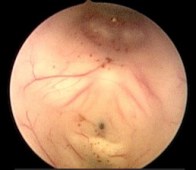

c’est l’indication reine de la ventriculo-cisternostomie endoscopique. cette intervention est efficace, avec amélioration clinique nette et rapide, dans la grande majorité des cas.